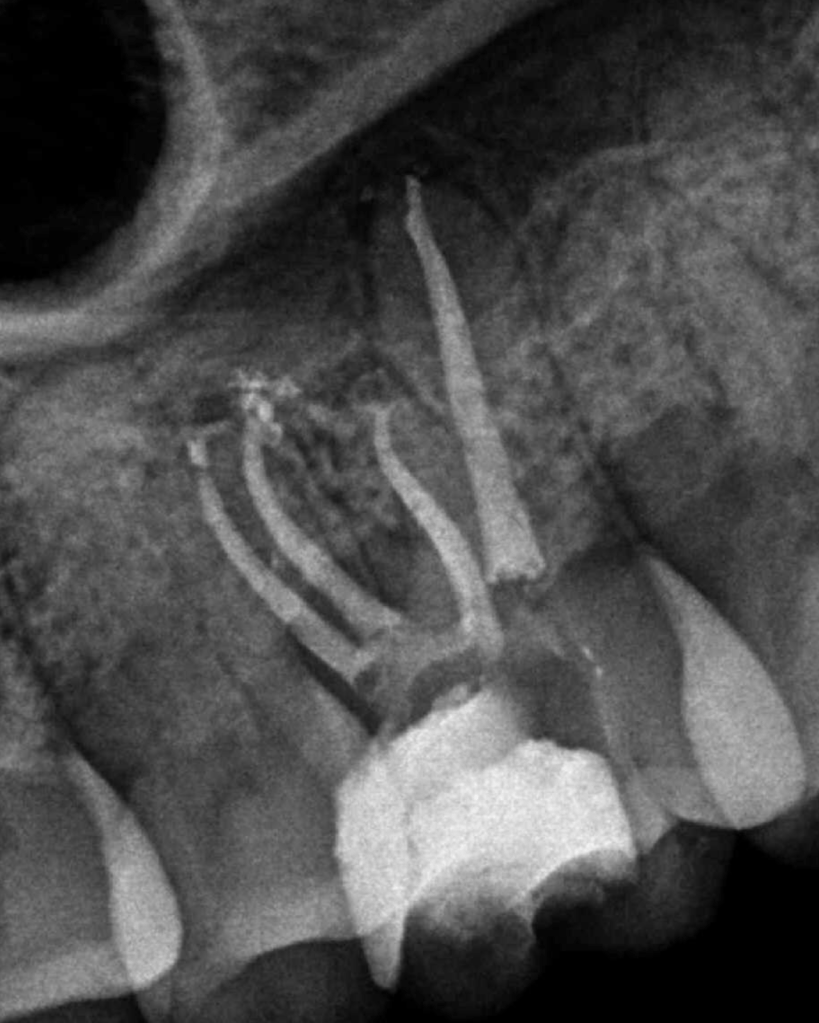

Molar superior anatomía compleja